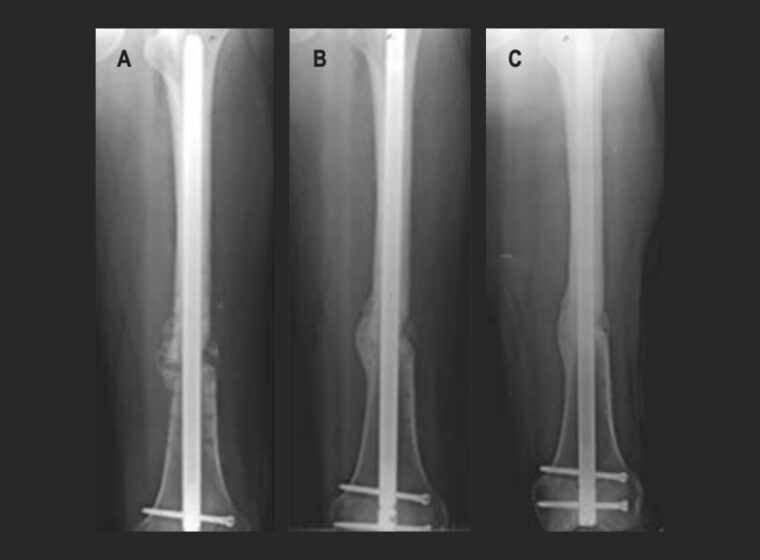

Ortobiológicos y aloinjertos en pseudoartrosis con pérdida ósea diafisaria femoral

Técnicas bioactivas utilizando esponjas de gelatina (Gelfoam®) como andamio para regeneración ósea

Preguntas frecuentes Utilizamos técnicas combinadas: injertos óseos (autólogos o aloinjertos), ortobiológicos (PRP, células madre) y fijación biomecánica avanzada. En casos complejos, aplicamos estimulación eléctrica o ultrasonido focalizado.